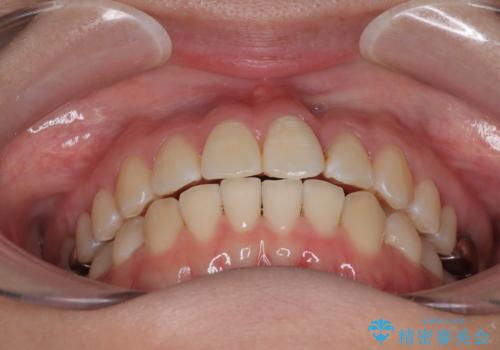

矯正治療期間はわずか10か月と、比較的短期間で終了しました。

前歯のデコボコがなくなり、見た目の印象が大きく変わっただけでなく、歯磨きがしやすくなり、むし歯や歯周病のリスクが大きく減少しました。